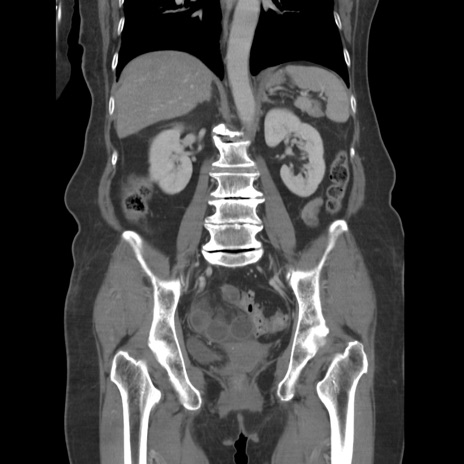

症例19(冠状断像)

【症例】80歳代女性

【主訴】下腹部痛

【現病歴】約8時間前より下腹部痛の出現あり、救急外来受診。

【既往歴】両側付属器切除

【身体所見】意識清明、下腹部正中に手術痕あり、その部位に一致して圧痛と反跳痛あり。腸蠕動音は亢進。

【データ】WBC 9300、CRP 0.15